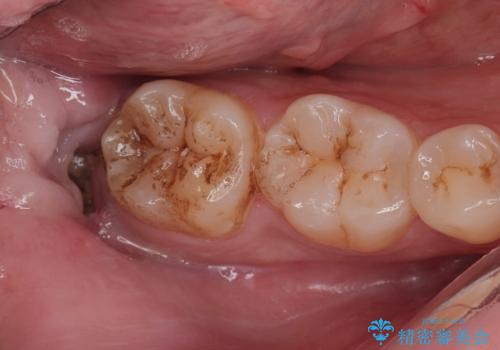

Dr. 松本麻里の症例写真

担当医 松本麻里<2025年12月27日更新>